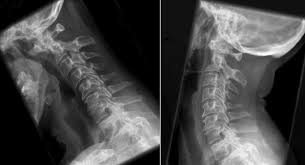

Reasons leading to Spine degeneration

Age and job characteristics are one of the most common causes leading to spine degeneration. The disease at serve level can cause complicated complications such as headache, dysphagia, nausea, dizziness,...

Spine degeneration (also called degeneration of spinal column) is one of the names of degenerative conditions of the spinal column due to various reasons related to works, activities or ages....